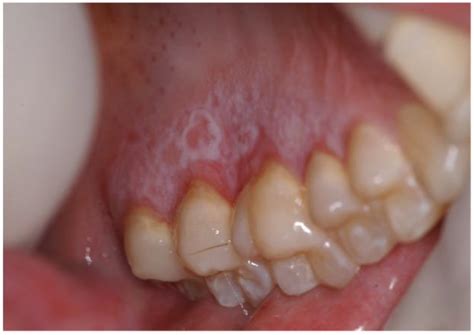

What Is Transient Lingual Papillitis? Transient lingual papillitis (TLP) is a minor health condition that causes small, painful bumps on your tongue that are red, white, or yellow. Also called lie ...

Your tongue does far more than help you taste food or speak; it also acts as a natural health indicator. Subtle changes in its colour, texture, and overall appearance can offer important clues about ...